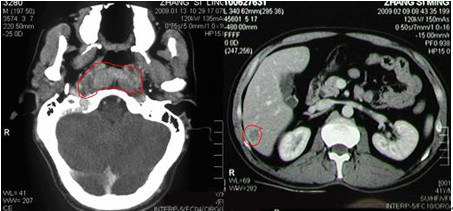

【检查】肿块约2.1×4.4cm,质硬,固定。查鼻咽镜加病理组织活检诊断:(鼻咽部)非角化癌(分化型)。查鼻咽CT:鼻咽癌。

【诊断】鼻咽癌晚期(鼻咽癌原肝右叶转移)。

【以往治疗】 当地医生建议予CF+5-Fu+L-OHP+THP方案二周期,化疗后回缩性涕血消失,左颈肿块缩小超过50%,达部分缓解。后采取放射治疗,放疗后出院,口腔黏膜干燥,恶心,予对症处理后减轻。之后患者因呕吐拒绝化疗,颈部仍可触及一个1.1×1.4厘米肿大淋巴结,彩超提示:肿大淋巴结血流丰富,并做CT,示:见肝右叶转移瘤。为求进一步治疗,来到广州中医药大学金沙洲医院肿瘤综合诊疗中心,采取WB-1无创全身热疗系统进行治疗。

左图为确诊鼻咽癌,右图为见肝右叶转移瘤